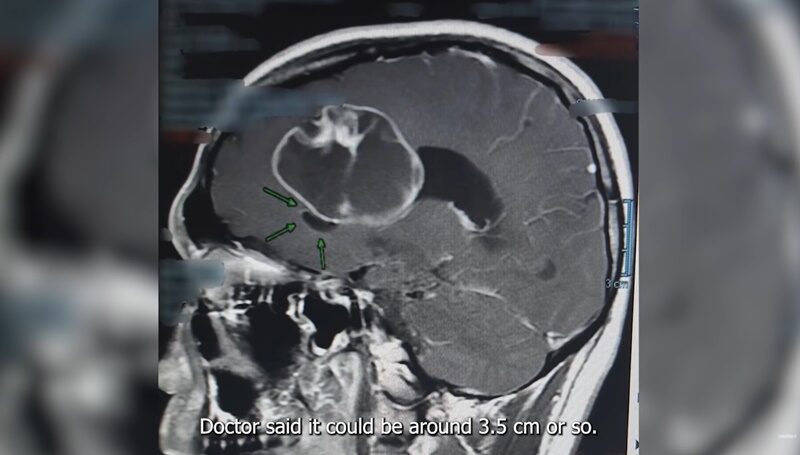

โดยหมอก็บอกว่าอาการไม่น่าจะดี อยากทำเอ็มอาร์ไอ ผลออกมาหมอโทรบอกฟังเสียงรู้เลยว่าแย่แน่ๆ ตกใจมากไปดูผลพร้อมกับหมอ สิ่งที่ไม่คาดคิดเกิดกับเราจริงๆ เจอเนื้องอกในสมองผม ตกใจกว่านั้น คุณหมอบอกว่าเป็นคุณหมอจะไม่รออะไรแล้ว ต้องผ่าตัดเปิดสมองเลย

มาร์กี้ เผยว่า ดูในภาพเนื้องอก ใหญ่มาก 3.5-4 ซม. ขณะที่ ป๊อก เผยว่า หมอบอกขนาดประมาณลูกปิงปอง ผมเคยมีประสบการณ์ไม่ค่อยดี มีคนในครอบครัวผม มีคนผ่าตัดสมองแล้วไม่ฟื้นกลับมา เป็นประสบการณ์ที่น่ากลัวมาก ถ้าผมโชคไม่ดีหละ ไม่ฟื้นกลับมา จะทำยังไง ยังไม่ได้เตรียมตัวเตรียมใจตรงนั้นเลย สิ่งที่ลอยขึ้นมาทันใดคือหน้าลูกครอบครัวผม

24 พ.ย.64 หลังการผ่าตัดสมอง ป๊อก เผยว่า ผ่าตัดครั้งนี้ค่อนข้างซีเรียส ผ่าตัดใหญ่ พอเห็นของจริงไซซ์ลูกเทนนิส ไม่ใช่ลูกปิงปอง

มาร์กี้ ช่วยเล่าตอนฟังผลเสียงว่า มาถึงตอนแรกหมอบอกว่าไม่ใช่เนื้อร้าย เราก็ถามแต่ก่อนหน้านี้สีหน้าหมอเครียดมาก เกิดอะไรขึ้นตอนนั้น เขาบอกว่าตอนดูฟิล์มเอ็มอาร์ไอแล้วเห็นชิ้นเนื้อ เห็นว่าสมองมีเลือดออกด้วยข้างใน มันเป็นอาการของคนที่เป็นมะเร็งระยะสุดท้าย ซึ่งมีอายุได้ไม่เกิน 2 ปี สำหรับคนไข้ที่เป็นแบบนี้ มันรักษาไม่ได้ด้วย เขาเลยไม่รู้จะพูดกับคุณปู่ยังไง จะให้คุณปู่มาฟังกับกี้ 2 คนไหวไหม เขาเลยอยากทำแฟมิลี่มีตติ้ง แต่พอผลออกมาไม่ได้เป็นอย่างที่คิด เขาก็แปลกใจเหมือนกันว่าไม่ได้เป็นได้ยังไง ทุกอย่างมันไปทิศทางนั้นแล้ว